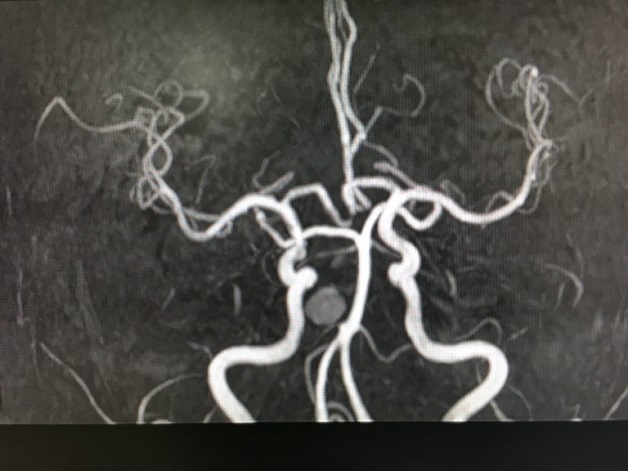

Hình ảnh mạch máu não trên phim chụp MRA sọ não. (ảnh minh họa)

Hiên nay, phương pháp tầm soát não bộ được ứng dụng với máy chụp cộng hưởng từ MRI sọ não và chụp cộng hưởng từ mạch máu não (MRA). Là phương pháp an toàn, cho kết quả có độ chính xác cao và có thể áp dụng trên mọi lứa tuổi từ người già, trẻ nhỏ và cả phụ nữ đang mang thai.